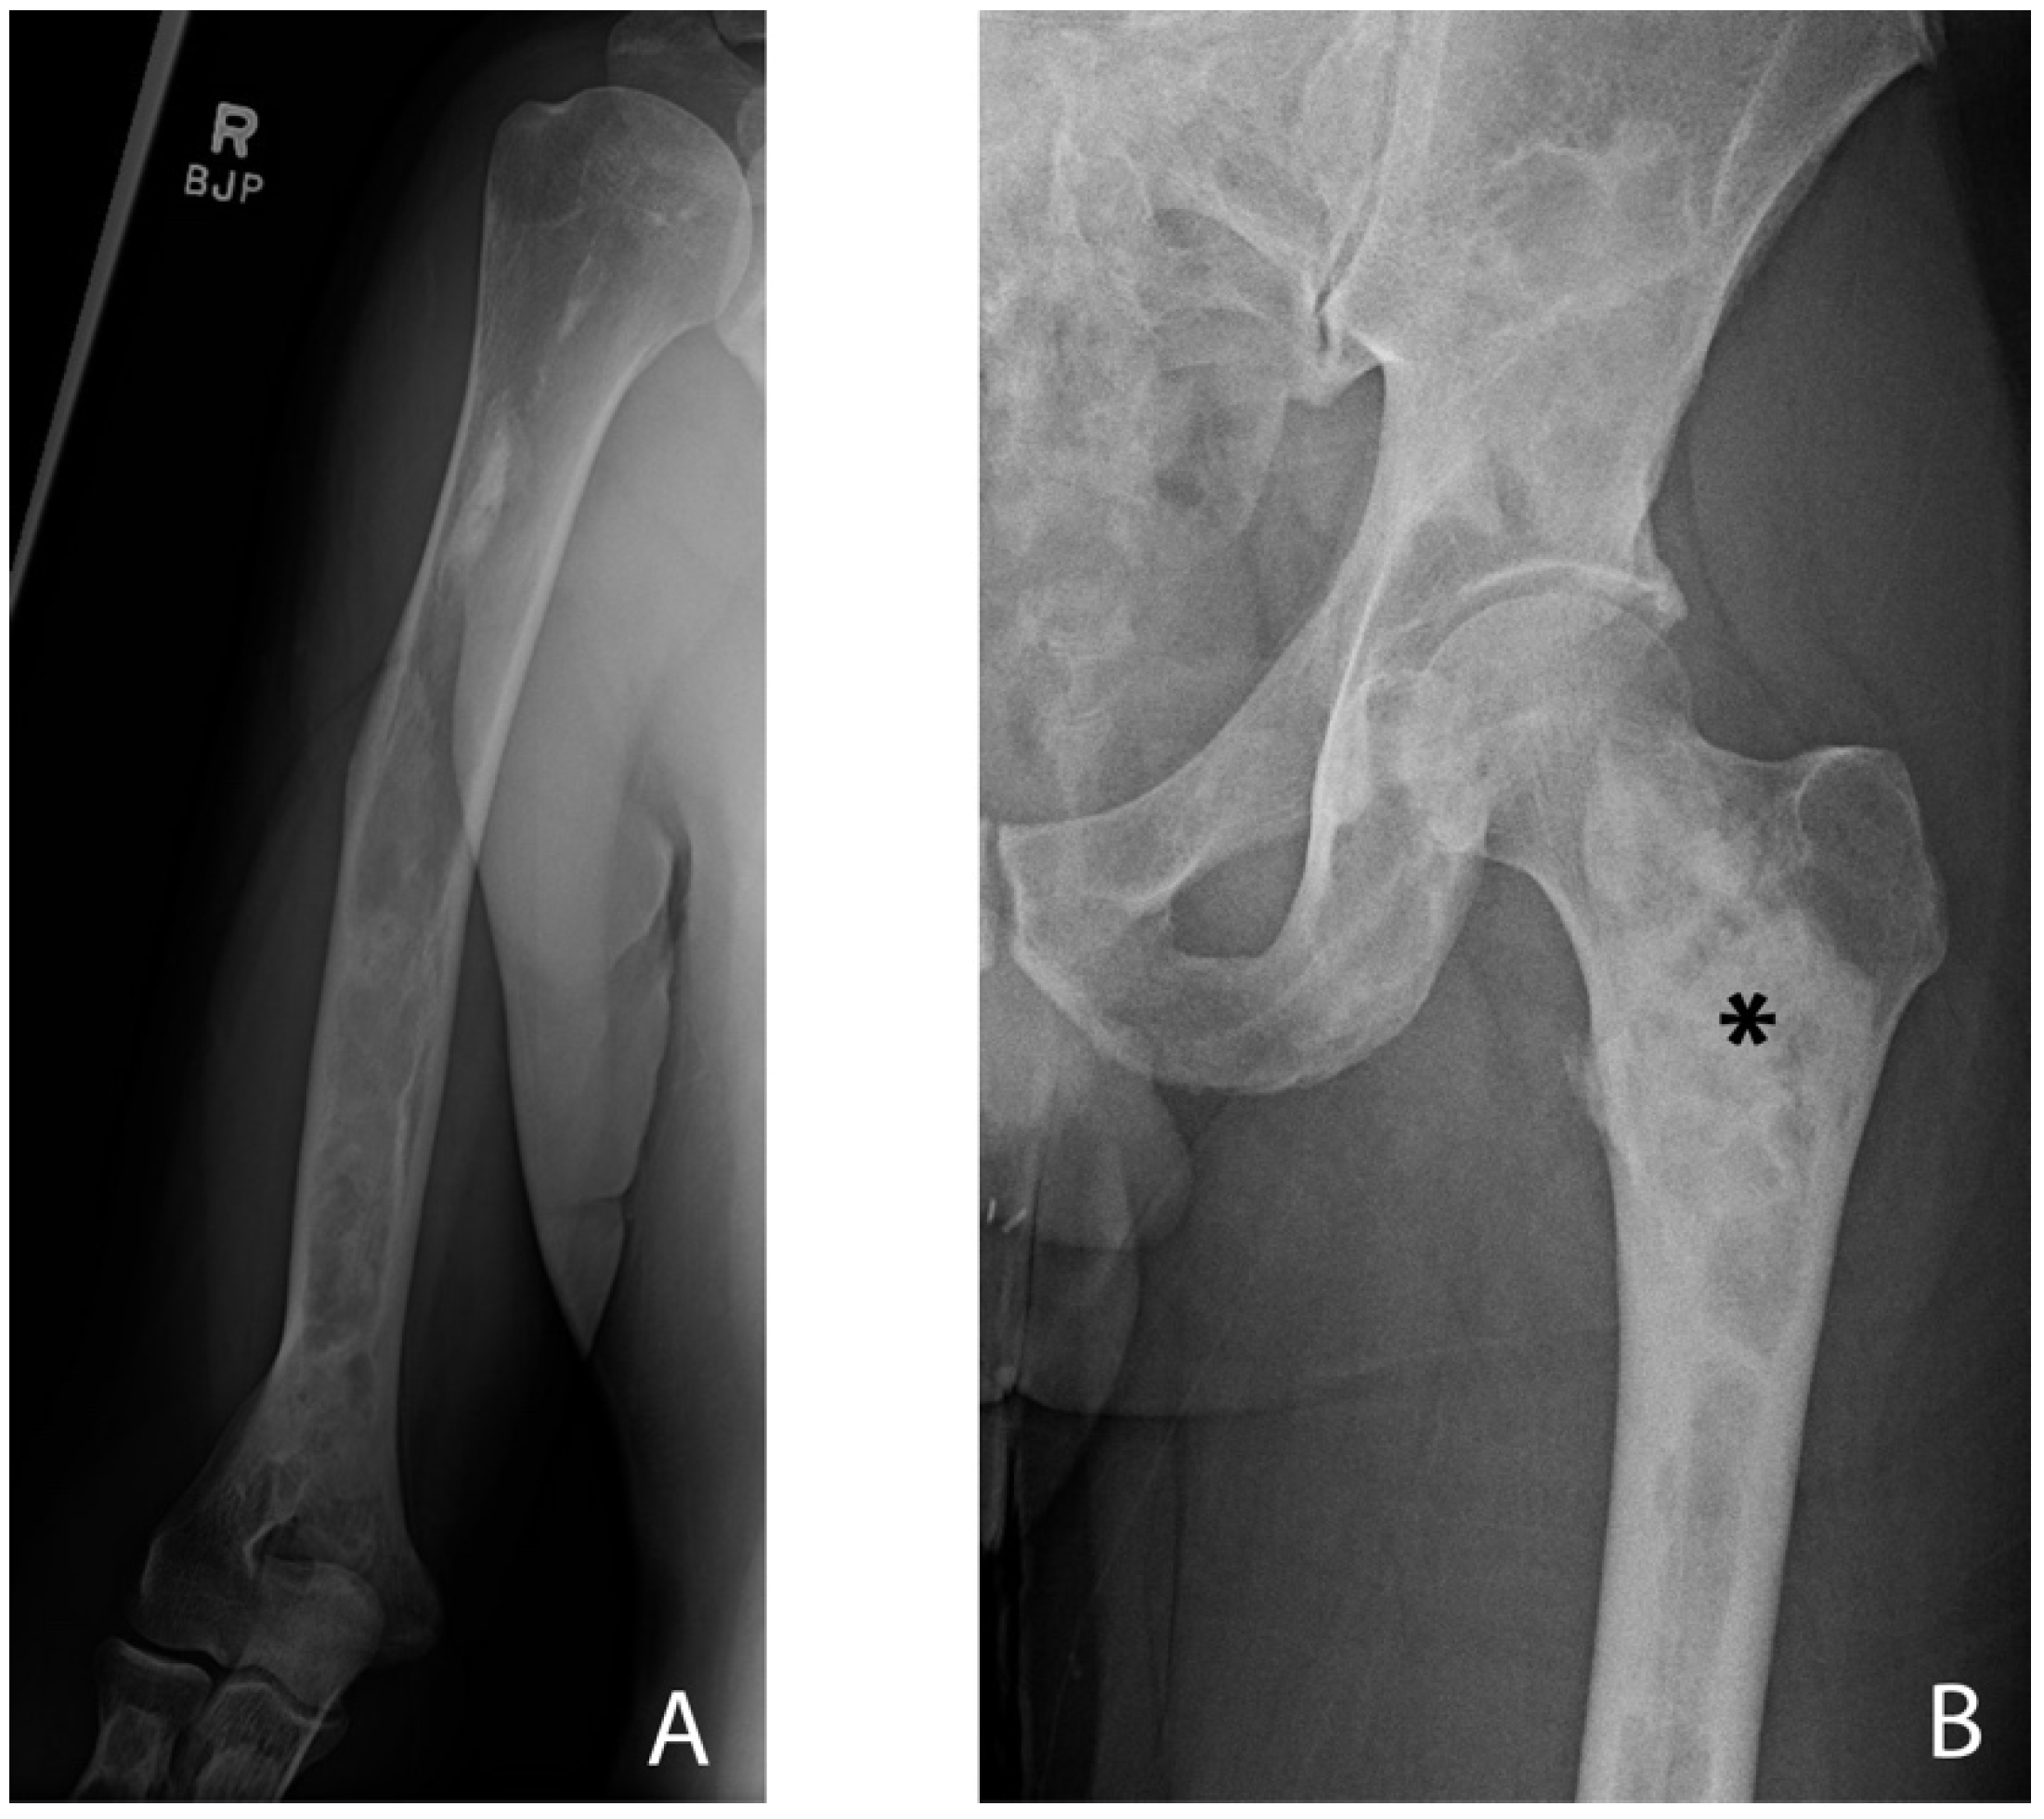

3.1. Appendicular Manifestations of FD/MAS

- Wang, Y.; Luo, Y.; Min, L.; Zhou, Y.; Wang, J.; Zhang, Y.; Lu, M.; Duan, H.; Tu, C. The West China Hospital radiographic classification for fibrous dysplasia in femur and adjacent bones: A retrospective analysis of 205 patients. Orthop. Surg. 2022, 14, 2096–2108. [Google Scholar] [CrossRef]

- Zhang, X.; Chen, C.; Duan, H.; Tu, C. Radiographic classification and treatment of fibrous dysplasia of the proximal femur: 227 femurs with a mean follow-up of 6 years. J. Orthop. Surg. Res. 2015, 10, 171. [Google Scholar] [CrossRef]

- Ippolito, E.; Farsetti, P.; Boyce, A.M.; Corsi, A.; De Maio, F.; Collins, M.T. Radiographic classification of coronal plane femoral deformities in polyostotic fibrous dysplasia. Clin. Orthop. Relat. Res. 2014, 472, 1558–1567. [Google Scholar] [CrossRef]